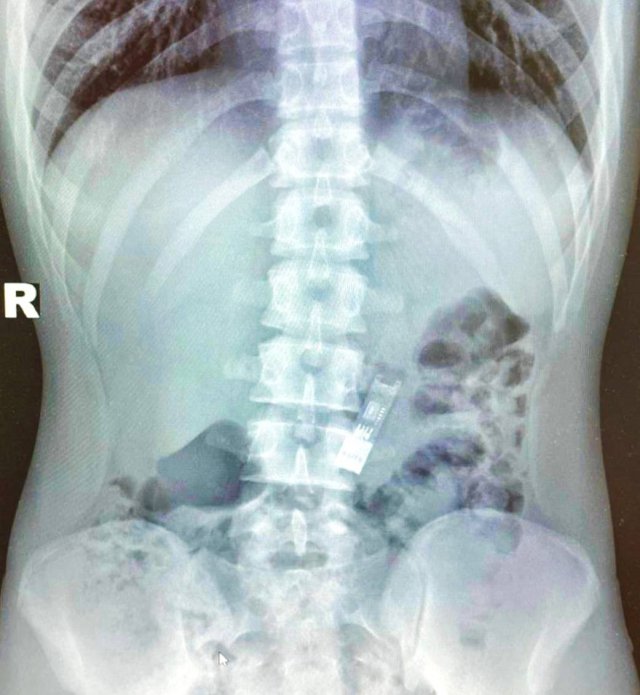

В одной из школ Подмосковья произошел курьезный инцидент: 16-летний подросток случайно проглотил флешку с домашним заданием по информатике. Как выяснилось, он просто баловался, но флешка "не захотела" покидать его организм естественным путем. Родителям пришлось везти сына в больницу, где врачи извлекли флешку эндоскопическими щипцами. Операция заняла всего 15 минут, а школьника выписали уже на следующий день. Самое удивительное – флешка оказалась рабочей, и подросток всё-таки сдал свою домашку!